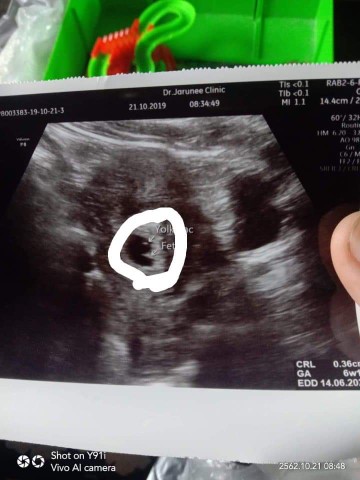

บ้านนี้เจอ6วีคค่ะ เจอทั้งถุงและตัวลูกน้อย ที่วงกลมไว้คือเจ้าตัวเล้กค่ะ